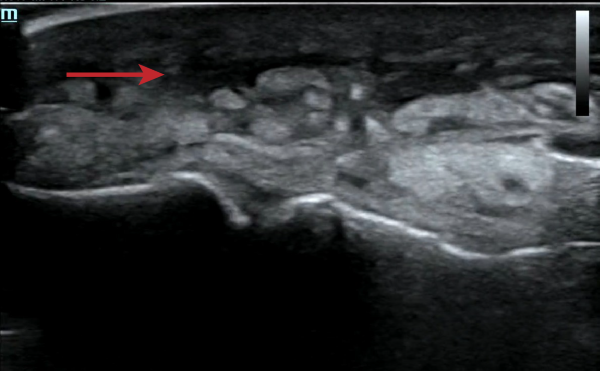

To further assess the extent of the wound, the emergency physician performs a point-of-care ultrasound (POCUS) to the lateral aspect of the right foot using the linear probe in the musculoskeletal (MSK) preset. Within the subcutaneous tissue, numerous hyperechoic foci are present with posterior dirty shadowing (Image 1). Additionally, an anechoic layer is visualized at the suprafascial layer (Image 2).

Image 2. Anechoic fluid layer in the suprafascial plane (red arrow)

To optimize the ultrasound settings, a linear probe should be used and set to the musculoskeletal (MSK) setting. Classic POCUS findings of NF include fascial thickening and subcutaneous tissue thickening. In gas-forming infections, the most specific finding is subcutaneous air, which appears as hyperechoic foci with posterior dirty shadowing. In contrast, in non-gas forming infections, the key finding is anechoic fluid tracking along the fascial plane, with fluid collections >4 mm considered significant.8-10